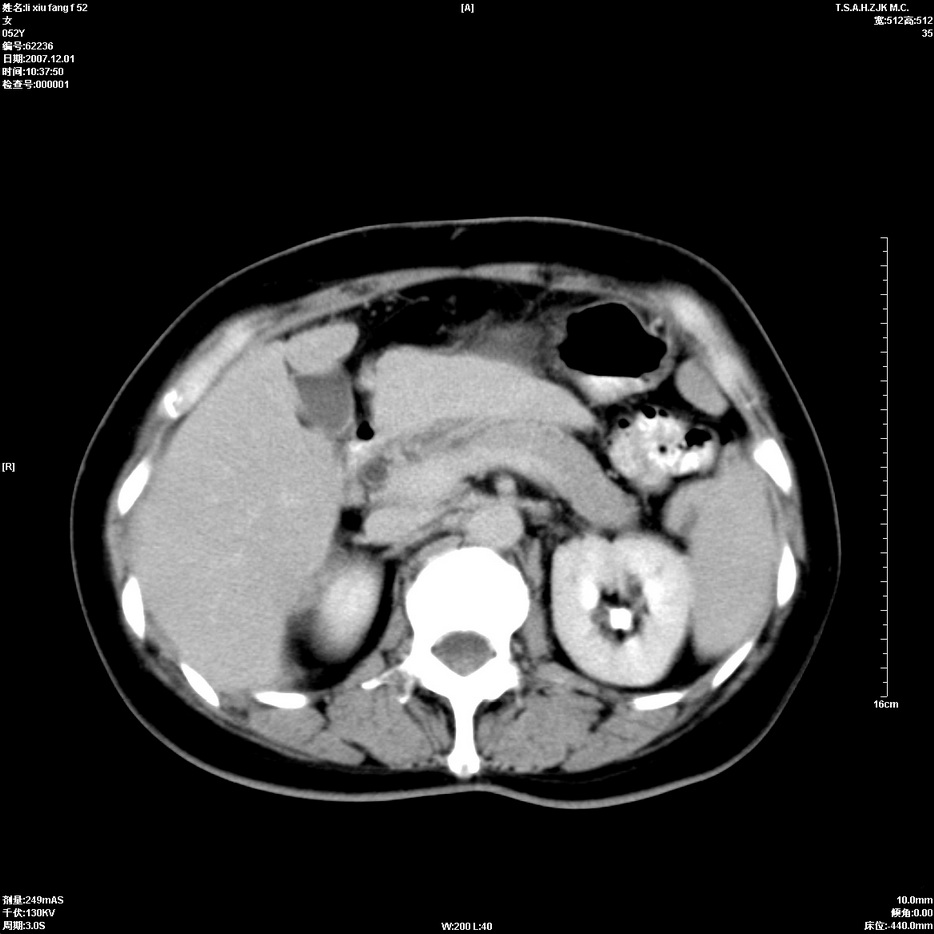

标题: CT12858:女,52岁,胎甲球蛋白861肝左叶占位,肝癌。下腔静 [打印本页]

标题: CT12858:女,52岁,胎甲球蛋白861肝左叶占位,肝癌。下腔静

肝左叶巨大低密度灶肿块,增强符合快进快出表现,有动静脉交通支;静脉期,下腔静脉内有充盈缺损,afp明显升高,支持肝癌并下腔静脉癌栓形成。

以下是引用拾荒者在2008-4-15 22:57:00的发言:[br]肝左叶巨大低密度灶肿块,增强符合快进快出表现,有动静脉交通支;静脉期,下腔静脉内有充盈缺损,afp明显升高,支持肝癌并下腔静脉癌栓形成。